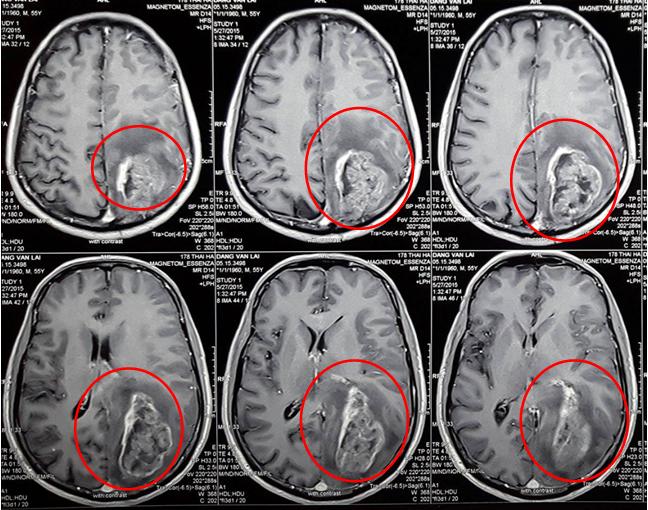

• Hình ảnh phim chụp cộng hưởng từ sọ não trước mổ cho thấy khối u não vị trí thùy đỉnh - chẩm bên trái, kích thước 45 x 56mm, ngấm thuốc mạnh, phù não rộng xung quanh.

Hình 1: Hình ảnh u não thùy đỉnh - chẩm trái (vòng tròn đỏ)